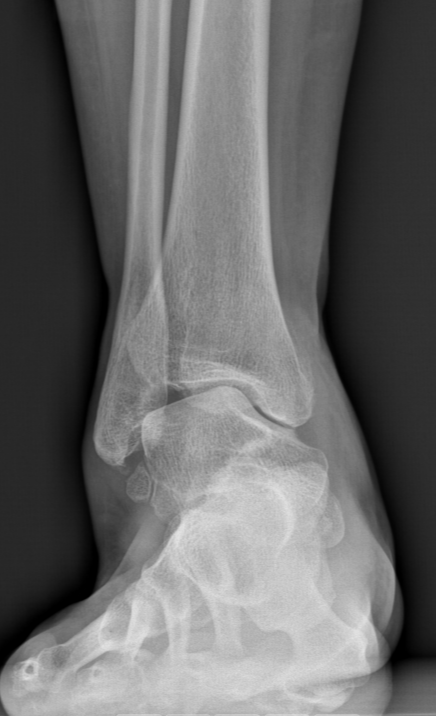

第一台手术的患者是位75岁的叔叔,被“脚脖子”痛缠了4年,疼得越来越厉害,病情已经到了严重阶段。

术前踝关节CT

术前后足力线X线

武勇主任团队给他做了3D打印导板辅助下人工全踝关节置换术。

这种手术适合踝关节病严重的患者,通过替换病变的关节结构,能帮着缓解疼痛、恢复关节活动,让老人日常走路更自在些。

术前踝关节侧位X线

术前踝关节正位X线

术后侧位X线

术后正位X线